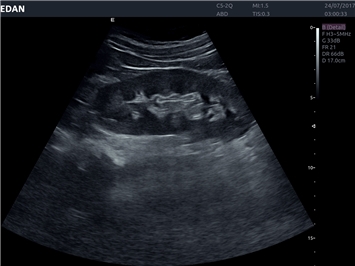

• Общей визуализации

• Акушерства и гинекологии

• Кардиологических исследований

• Сосудистой диагностики

• Педиатрии

• Исследования малых органов